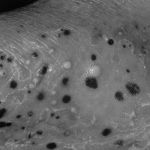

Псоріаз на стопі виглядає як червоне потовщення шкіри, покрите бульбашками з жовтуватою рідиною. Такий вид - різновид пустулезного псоріазу та зустрічається рідко.

А також буває псоріаз стоп вульгарного типу, при якому шкіра потовщена і червона, а зверху сухі лусочки:

Псоріаз стопи: фото

Дивіться фото, як виглядає псоріаз на стопах ніг:

Псоріаз на стопах виглядає як червоне потовщення шкіри, покрите зверху лусочками або бульбашками з рідиною.